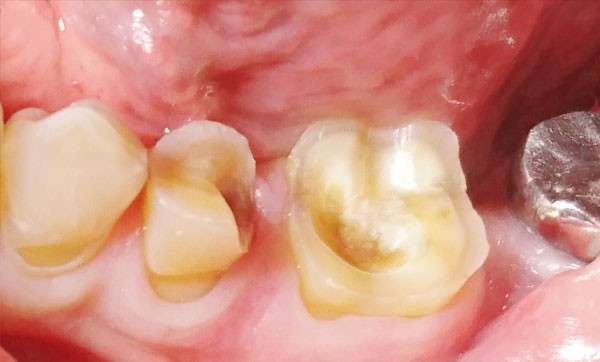

Nous nous intéresserons au concept de préparations assistées par guidage (PAG) développé par le Dr Jacques Raynal, permettant de normaliser les RPC indirectes aux critères d’exigences de la chaîne de CFAO. Nous illustrerons nos propos par un cas clinique, avec la réalisation de deux RPC indirectes de type V-Prep sur une deuxième prémolaire mandibulaire gauche (35) et sur une première molaire mandibulaire gauche (36).